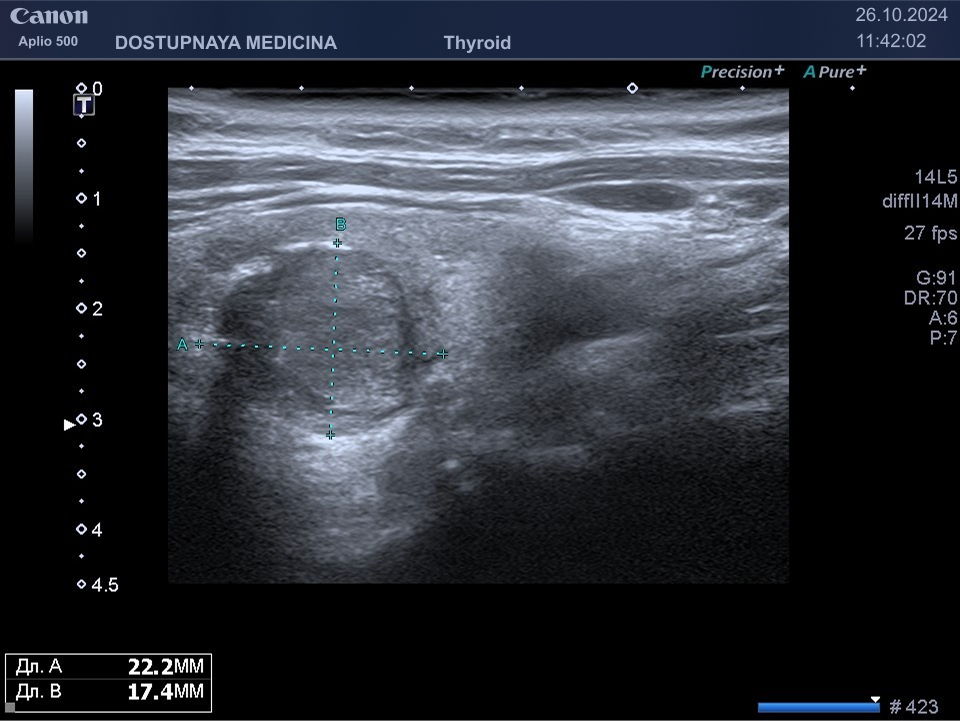

В ультразвуковой диагностике существует классификация образований щитовидной желзы по TIRADS, которая по различным критериям определяет степень онкоопастности того или ионого узла. При оценке учитывается эхоструткура образования ( кистозная, губчатая, солидная или солидно-кистозная), эхогенность ( анэхогенное, гиперэхогенное, гипоэхогенное), пространственная ориентация горизонтальная, вертикальная, неопределённая), контуры образования (ровные, дольчатые, зазубренные с острыми углами), наличие эхогенных включений( макрокальцинаты, микрокальцинаты, периферическая кольцевидная кальцификация). В зависимости от этих критериев выделяют различные категориии объёмных образований в щитовидной железе:

TIRADS 3 – низко подозрительное образование, требующие динамическое наблюдение и тонкоигольной биопсии при размерах узла больше 2.5 см.

TIRADS 4 – умеренно подозрительное образование, требующие динамическое наблюдение и тонкоигольной биопсии при размерах узла больше 1.5 см.

TIRADS 5 – высоко подозрительное образование, требующие динамическое наблюдение и тонкоигольной биопсии при размерах узла больше 1 см.

Большинство узловых образований в щитовидной железе не нуждаются в лечении и требуют лишь наблюдения путём повторного ультразвуковых исследований.

При подозрении на озлокачествление и увеличении узла в размерах требуется тонкоигольная пункционная биопсия с полседующим цитологическим исследованием, полученного материала.